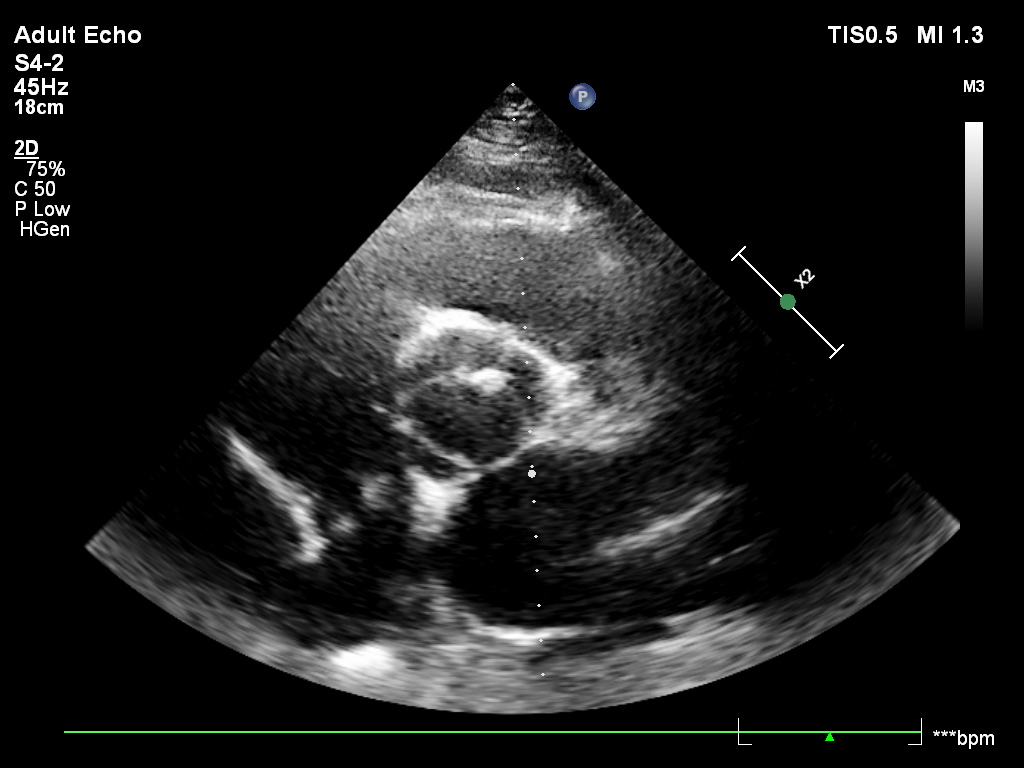

Przypadek 2.A

Przypadek 2.B

Przypadek 2.C